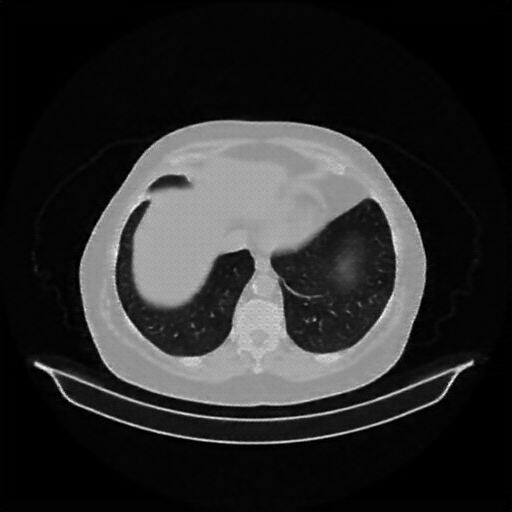

Generated VENOUS CT scan (A→B translation)

Lung window (WL -600, WW 1500 β†’ Low βˆ’1350, High +150)